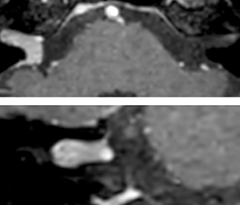

Giant cell arteritis

The 3D TSE T1w black blood MSDE sequence with fat suppression has an isotropic 0.8 mm voxel size and sagittal oblique and axial reformats are made. The images show superficial temporal artery thickening and peri-arterial fat infiltration. The 3D TSE PDw black blood MSDE with fat suppression has 0.55 mm isotropic voxels. The images shows focal involvement of the frontal branch of the superficial temporal artery.

3D TSE T1w BB MSDE

3D TSE PDw BB MSDE